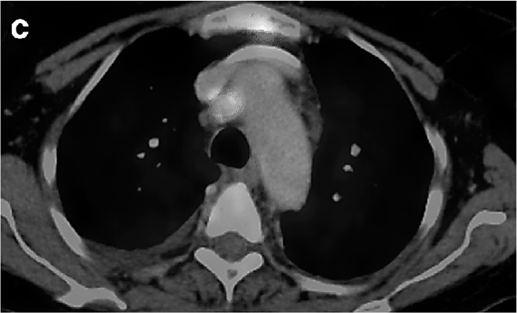

Um paciente de 62 anos de idade, tabagista ativo, cerca de 180 anos-maço, queixa-se de cansaço, tosse seca e perda de peso; por isso, procurou atendimento médico. O paciente referiu que pesava 100 kg e perdeu 10 kg. Realizou-se tomografia computadorizada de tórax, com evidência de lesão sólida de 2,1 cm em topografia de lobo inferior à direita, sólida, espiculada, com margens bem definidas e densidade de partes moles, assim como linfonodomegalia paratraqueal direita de 1,5 cm, paratraqueal esquerda de 1,2 cm e subcarinal de 2 cm. O paciente foi submetido a PET-CT de corpo inteiro, com evidência de hipercaptação de radiofármaco pela lesão (SUV 12) e pelo linfonodo representado na figura 2 a seguir.

Figura 2: PET-CT do tórax.

O linfonodo hipercaptante no PET desse paciente, representado na figura 2, trata-se do paratraqueal direito.